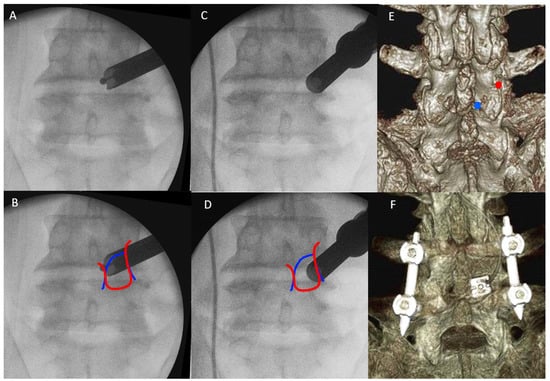

2.4.4. End Plate Preparation and Cage Insertion

3.2. Intraoperative Timing and Radiological Parameters